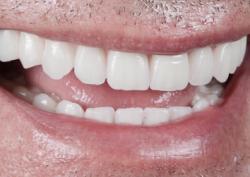

Примеры протезирования зубов

Каждый день мы помогаем восстанавливать улыбку нашим пациентам.